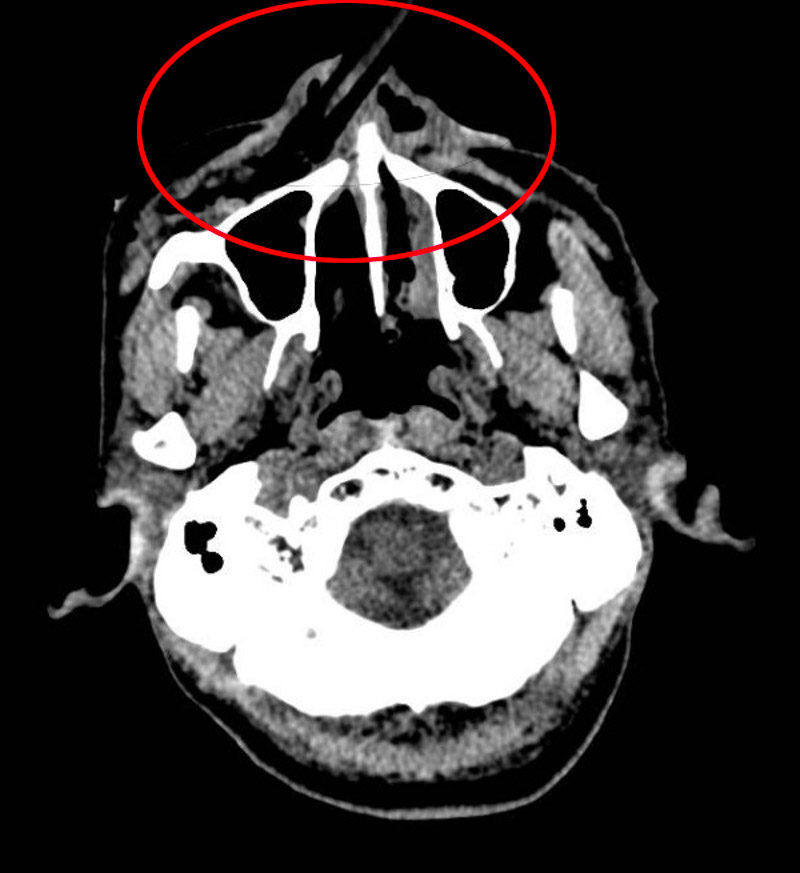

術中發現,竹棍由鼻尖處穿通鼻中隔插入鼻腔,貫穿鼻底黏膜,直達上頜竇前壁??谇豢浦魅嗡斡虏┦啃⌒囊硪淼貙⒅窆靼纬?,此時,仍有大量竹棍碎屑殘留在鼻腔內。由于竹棍在進入鼻腔后發生了折斷,很多碎屑插入軟組織,傷口深、視野差,清理難度大。如果異物清除不干凈,會在創口內持續發炎,導致二次手術。